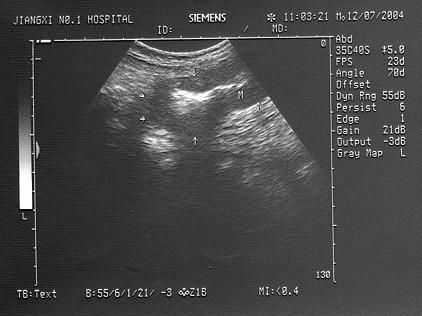

问题 女,35岁,上腹疼痛不适十年余,加重一月。结合超声声像图,诊断为?(?)

选项 A.胃癌 B.腹膜后肿块 C.左肝癌 D.胰腺癌 E.胃溃疡

答案 A